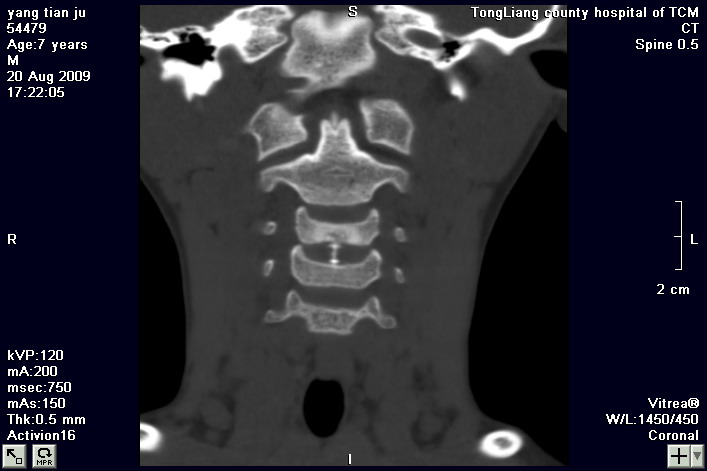

标题: PED2853:颈3/4椎间盘内高密度钙化灶,请各位会诊. [打印本页]

标题: PED2853:颈3/4椎间盘内高密度钙化灶,请各位会诊.

患儿,7岁,颈部疼痛3天,颈部活动受限.

本例应该是典型的儿童钙化性椎间盘病。

儿童钙化性椎间盘病发病年龄多在5~12岁,男女比例相当,大多数患儿发病主要表现为颈部疼痛,伴活动受限。少数有吞咽不适或肢体瘫痪。有一部分患儿无症状,是在其它检查时发现。病因尚不完全明了,可能的有:1、感染。2外伤。

儿童颈椎椎间盘钙化系一良性自限性疾病,可见于颈、胸、腰椎,以颈椎为多发,腰椎少见,多为单发。钙化位于髓核,也可累及软骨板和纤维环引起钙化主要发生于c 4~7  的髓核位于椎间隙正中或偏后,少数向前疝出,以后部多见,呈梭状、盘状、团块状或半环状;(2)颈椎生理曲度变直,椎间隙正常或增宽;(3)相邻椎体可变扁,局部凹陷变形,椎体前下缘鸟嘴状增生,或呈钳口状改变,椎前软组织增厚及环枢椎半脱位;(4)ct可清晰显示椎间盘髓核 位置的钙化灶及经破裂的纤维环向椎管内突出。(5)mri,钙化在t1及t2加权像上均呈低信号,并可见脊髓组织内异常信号。